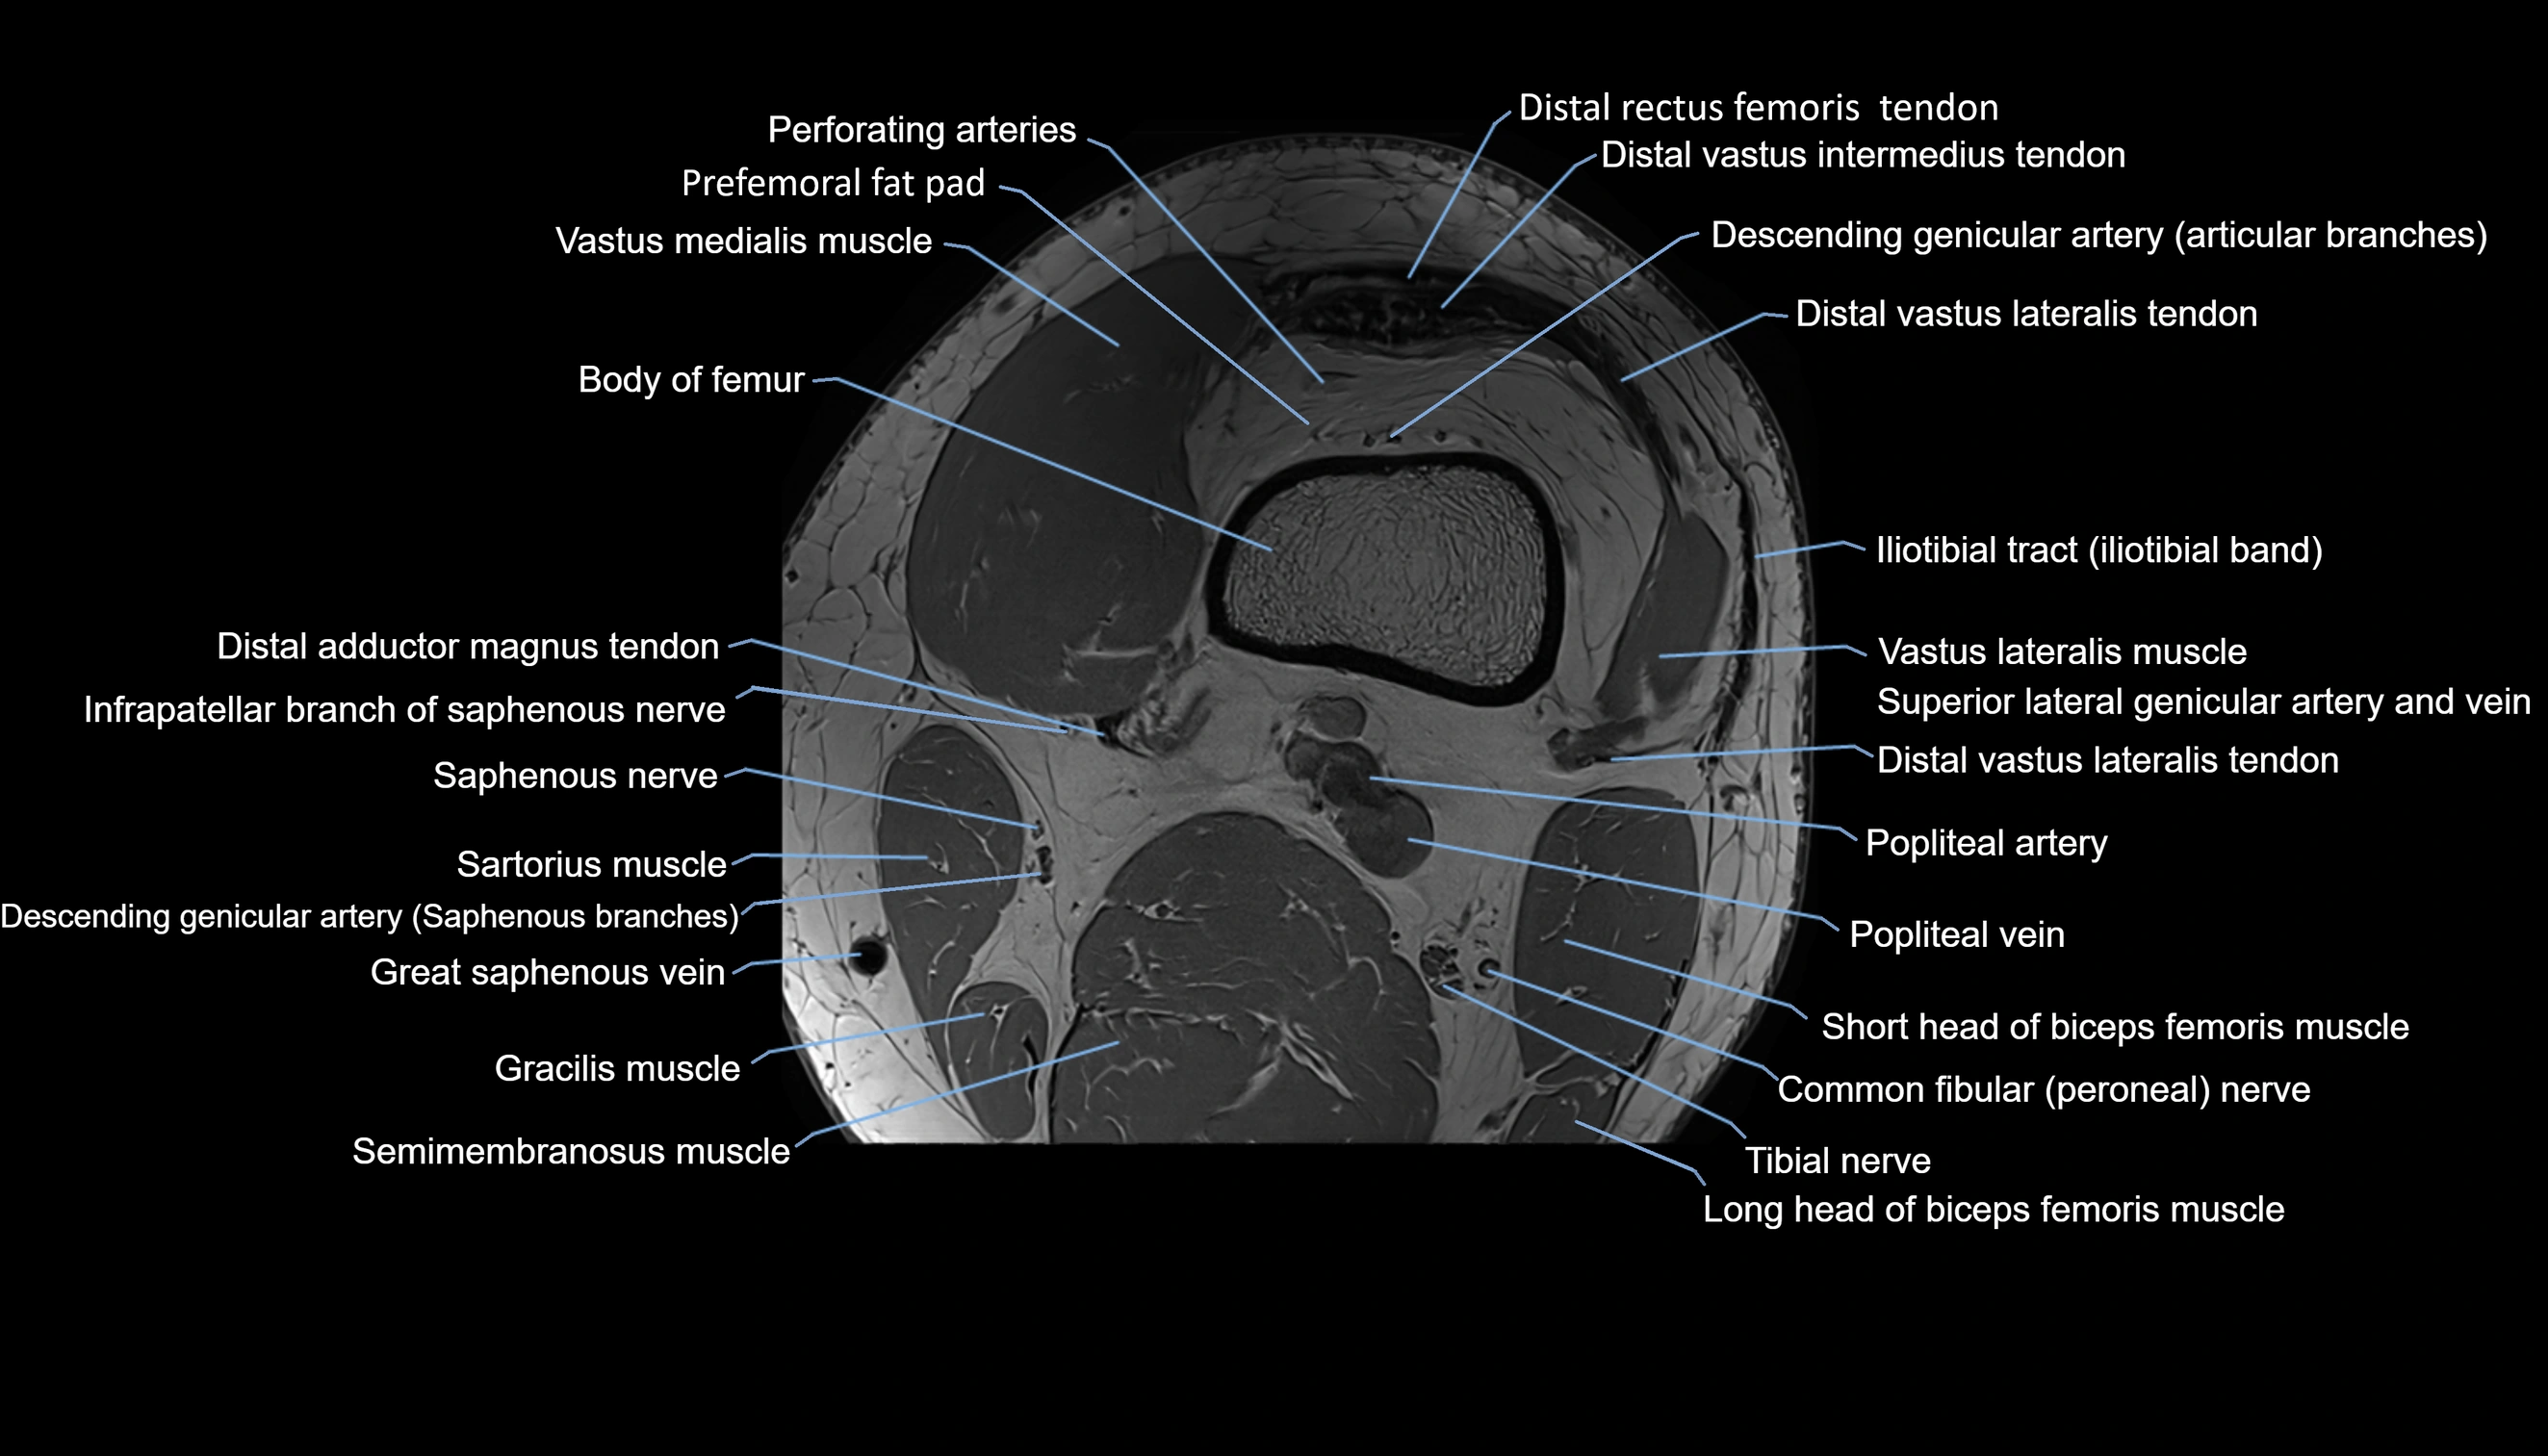

- Body of femur

- Distal adductor magnus tendon

- Distal rectus femoris tendon

- Distal vastus intermedius tendon

- Distal vastus lateralis tendon

- Descending genicular artery (Articular branches)

- Perforating Arteries (Knee joint)

- Prefemoral fat pad

- Vastus lateralis muscle

- Vastus medialis muscle